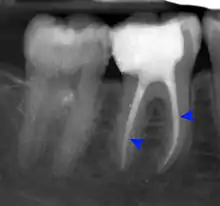

Decay (green) with apical abscess (blue)

Gutta-percha point indicating abscess origin